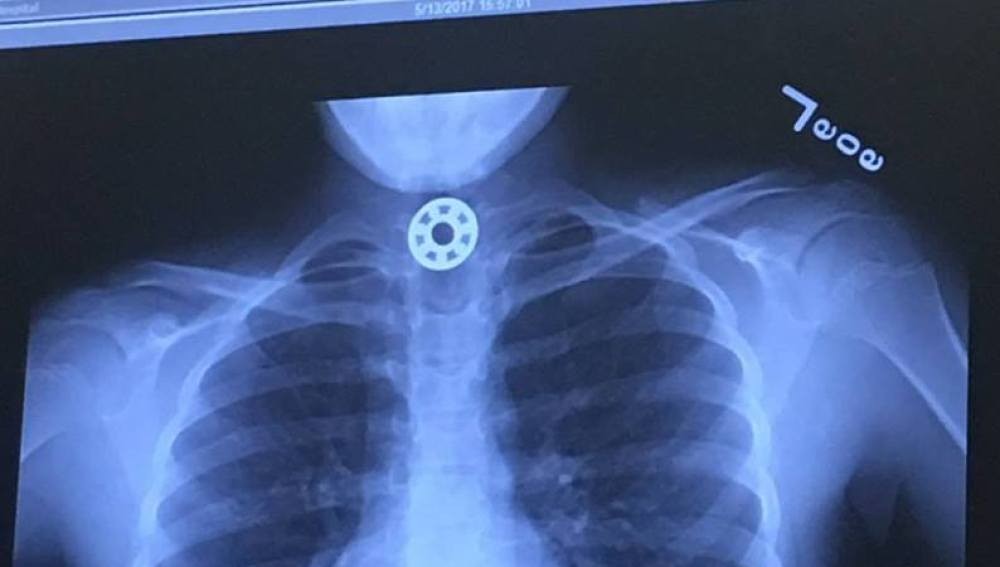

Mediante una radiografía encontraron que la nena tenía una una pieza similar a una arandela atascada en el esófago y le realizaron una endoscopia para retirarla.

Se trataba de una pieza del Fidget Spinner, que la chica se tragó en forma accidental al meterse el juguete en la boca para limpiarlo con saliva.